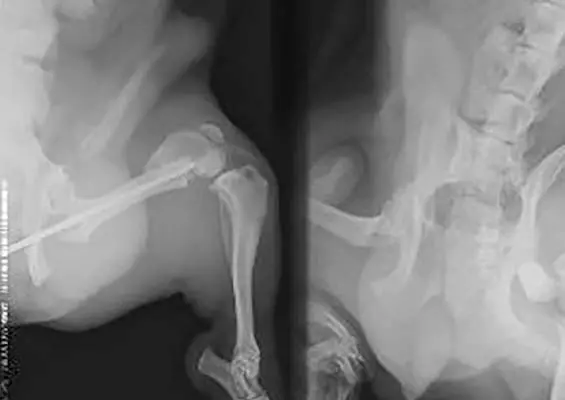

Lekarz weterynarii stawia rozpoznanie na podstawienie objawów klinicznych występujących u psa. Ważny jest też wywiad z właścicielem, aby dowiedzieć się, czy pies przebywał w ostatnim czasie w środowisku o większym zagęszczeniu psów. Nie ma dostępnych żadnych szybkich badań laboratoryjnych, które w 100% potwierdzałyby kaszel kenelowy. Stwierdzenie obecności w układzie oddechowym B. bronchiseptica nie jest jednoznaczne z postawieniem diagnozy, a badanie często daje wyniki fałszywie ujemne. Możliwa jest izolacja wirusów z dróg oddechowych, jednak badanie takie nie jest rutynowe. Teoretycznie można także określić wirusa, porównując miana przeciwciał fazy ostrej i po przechorowaniu. Obraz morfologii krwi oraz radiogram układu oddechowego również nie wykazują większych odchyleń od normy. Podczas badania klinicznego zauważa się tzw. kaszel reakcyjny, czyli odruch kasłania powstający w efekcie delikatnego podrażnienia krtani czy tchawicy. W diagnostyce różnicowej choroby wymienia się zadławienie, wymioty, duszność, poważne choroby serca czy inne choroby z układu oddechowego, na przykład bakteryjne zapalenie płuc czy nosówkę. Jeśli objawy są ciężkie, zaleca się wykonanie zdjęci...